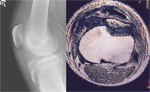

Pt is a 30-year-old competitive weight lifter with chronic patellar femoral pain. X-ray exam in the office revealed an accessory os of the patella. Clinical correlation revealed this to be the area of maximal tenderness on exam. After failing conservative management with extensive physical therapy, NSAID use, and inter-articular steroid injection, the patient elected to undergo arthroscopic excision of the patellar os.

Pre Operative X-Ray

Arthroscopic photos from the surgery show removal of the os. The spinal needle is used to localize the os and demonstrate that it is loose. It is then removed arthroscopically with a burr. Care is taken to not disrupt the dorsal capsule.